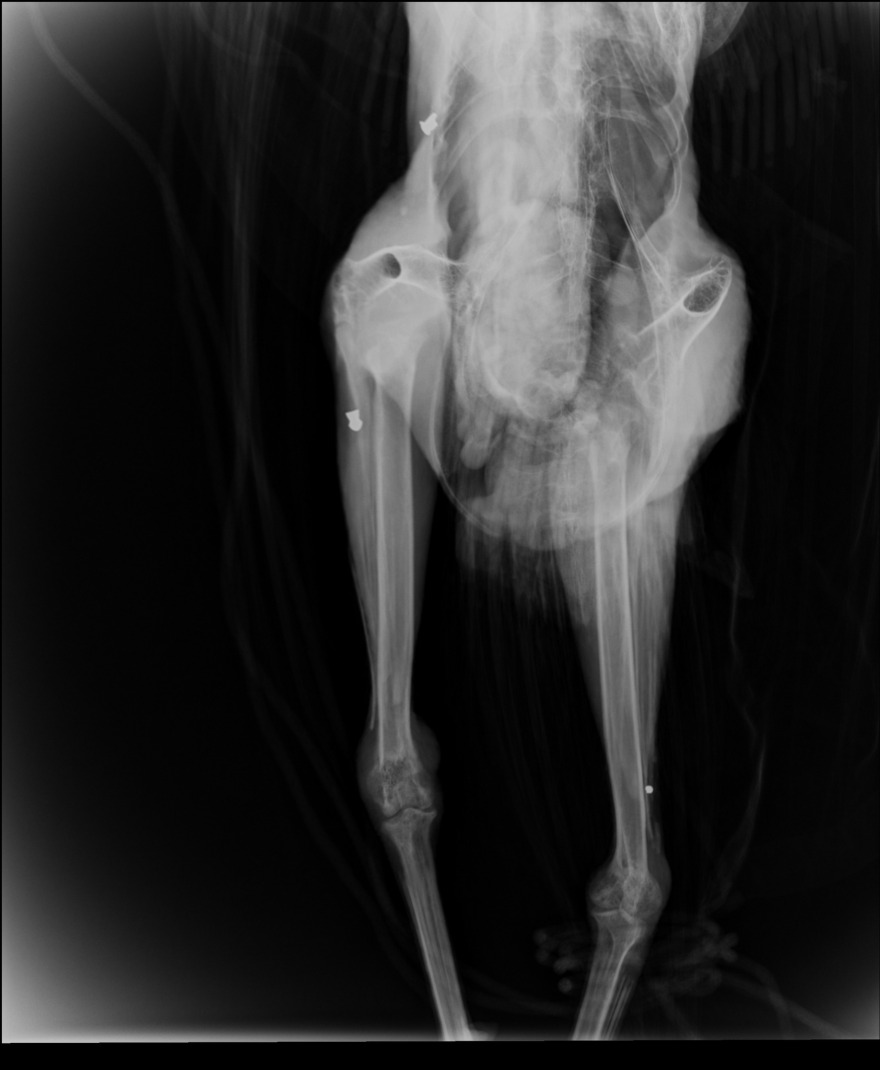

Το γεγονός επιβεβαίωσαν και σχετικές ακτινογραφίες που έδειξαν μάλιστα δυο βολίδες αεροβόλου κι ένα σκάγι.

Δείτε φωτογραφίες: